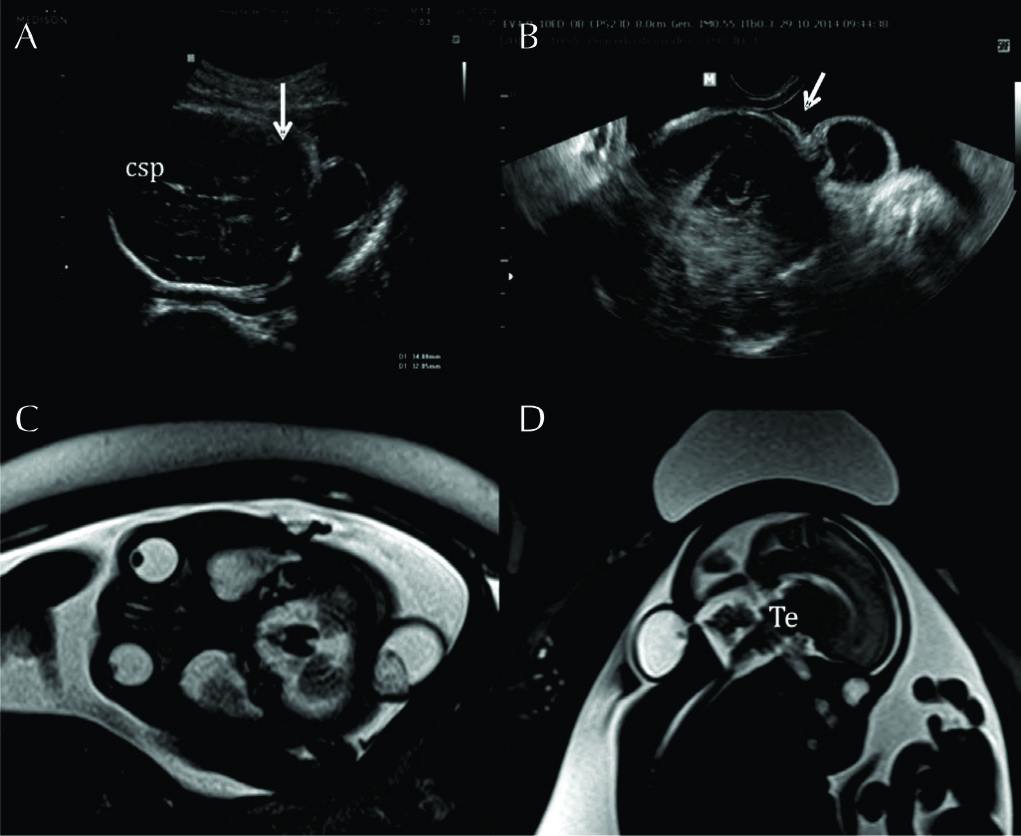

Figura 3

RM Fetal con Ventriculomegalia (Edad Gestacional: 28 semanas).

Imágenes seleccionadas de RMf en paciente referido por estudio ecográfico que muestra aumento del tamaño del sistema ventricular.

En A imagen en línea media donde se reconocen las estructuras normales: cuerpo calloso (CC), tronco encefálico (Te) y cerebelo (Ce) con su aspecto habitual.

En B el corte axial a nivel de los atrios ventriculares donde se evalúa el tamaño ventricular (16mm del lado izquierdo) y se reconocen la cisura inter-hemisférica completamente formada (CIE) y la cisura de Sylvio en la convexidad (CS).

En C y D cortes coronales que complementan la valoración anatómica. Luego del análisis preciso de todo el estudio no se encontraron otras anomalías asociadas.